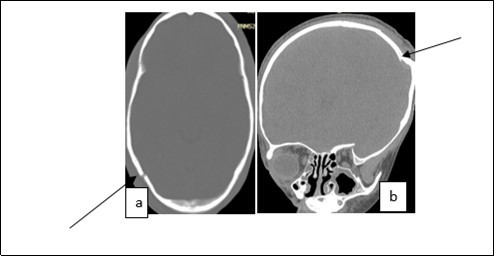

From the point of view of care, two (n=2) (10.52%) children received medical treatment compared to 17 (89.48%) children who received medical-surgical treatment. Neurosurgical treatment consisted of evacuation of the extra dural hematoma. This involved making a skin incision, trepanation (Figure 3 a), a preserved cranial bone flap, evacuation of the extra-dural haematoma (Figure 3 b), haemostasis either of the bone using bone wax or venous or arterial haemostasis by bipolar coagulation as appropriate, suspension of the dura mater (Figure 3 c), replacement of the bone flap (Figure 3 d) and finally suturing of the scalp in two planes. Figure 1, Figure 2, Figure 3.

Figure 1.Image of a brain CT scan without contrast, in a parenchymal window, axial view showing a right parietal extra dural hematoma associated with diffuse cerebral oedema, and subfalcorial brain schift

Figure 2.Image of a brain CT scan without contrast agent injection in a bone window, axial section showing a right parieto-occipital fracture (a), coronal section showing a left parietal skull depressed fracture (b)